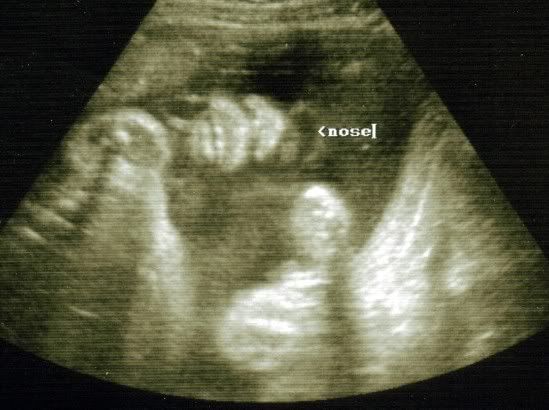

They did another U/S today so here are Braedin's latest pictures.

#2